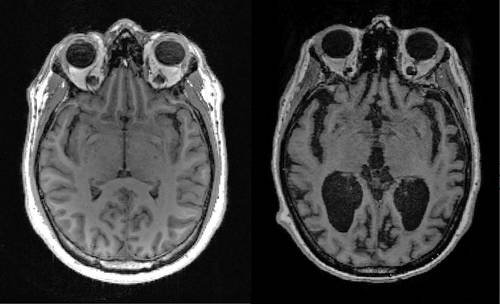

▲ En esta imagen sin fecha, cortesía de Timothy Rittman, de la Universidad de Cambridge, se observa la resonancia magnética de un cerebro sano (izquierda) y de uno enfermo (derecha) con grandes espacios negros donde el órgano está encogido. Foto Afp

Proteínas tóxicas llegan de forma temprana al cerebro y se acumulan durante décadas, revela análisis realizado con datos de tomografías y muestras post mortem de humanos